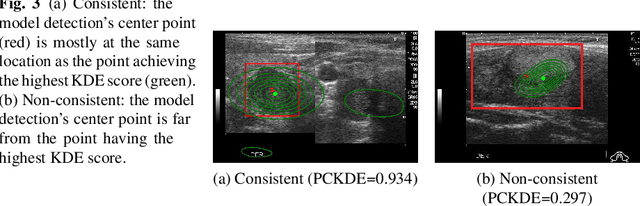

Abstract:The ability to explain the prediction of deep learning models to end-users is an important feature to leverage the power of artificial intelligence (AI) for the medical decision-making process, which is usually considered non-transparent and challenging to comprehend. In this paper, we apply state-of-the-art eXplainable artificial intelligence (XAI) methods to explain the prediction of the black-box AI models in the thyroid nodule diagnosis application. We propose new statistic-based XAI methods, namely Kernel Density Estimation and Density map, to explain the case of no nodule detected. XAI methods' performances are considered under a qualitative and quantitative comparison as feedback to improve the data quality and the model performance. Finally, we survey to assess doctors' and patients' trust in XAI explanations of the model's decisions on thyroid nodule images.